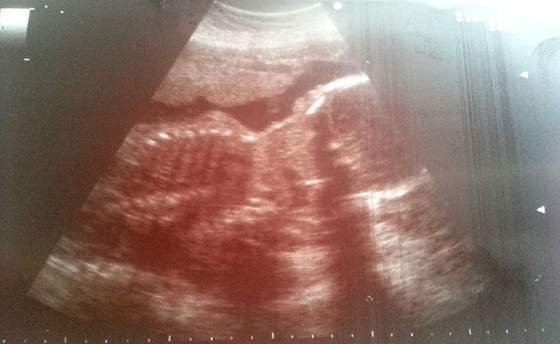

Wymiary (Matyldy rzecz jasna

):

wymiar dwuciemieniowy, czyli średnica główki BPD 68mm

obwód główki HC 244mm

obwód brzuszka AC 211mm

długość kości udowej FL 46mm

waga 932g

długość bez nóg 22cm, z nogami szacunkowo ok 40cm

wymiarowo jest większa o ok 1 tydzień, TP wg USG: 19.05.2013

Gin chciała nam buźkę pokazać ale mała nie chciała współpracowac i się pokazać